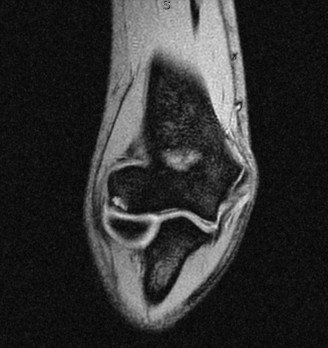

The patient undergoes conservative management consisting of rest, anti-inflammatory medications, and physical therapy. After six months, he is still not able to return to play and has progressively worsening symptoms with attempted throwing. He has a moderate elbow effusion as well as a 20-degree flexion contracture. An elbow MRI arthrogram is obtained and shown (Fig. 2–112). He elects to proceed with elbow arthroscopy. Intraoperative arthroscopic images are shown (Figs. 2–113 and 2–114).

Figure 2–112